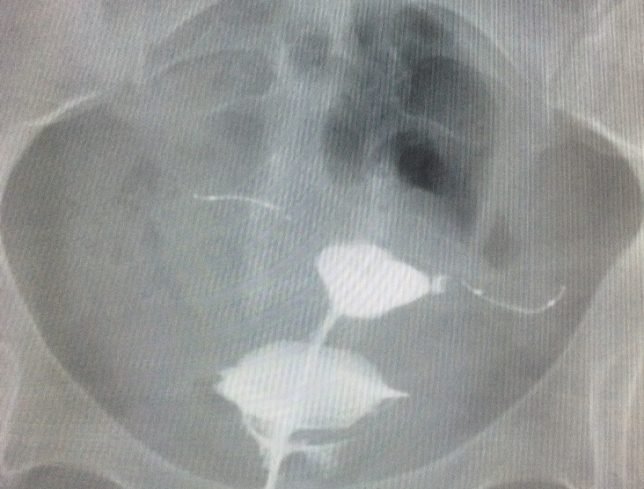

Hysterosalpingogram (HSG) is performed less commonly in modern gynecology than in the past, but it is still a valuable tool for some patients. A well performed HSG should be relatively painless and its results need to be correctly interpreted in context of what is already known about the patient. Here are four tips for performing an HSG.

1. Use a catheter.

Use a modern HSG catheter with an inflatable balloon tip rather than a reusable Cohen intrauterine cannula. Disposable catheters with a balloon can be purchased for about $15 or less and allow for the procedure to be performed with much less pain and discomfort than a traditional reusable cannula which requires a tenaculum to be placed on the cervix and instrumentation of the cervical canal in many cases. The balloon catheters are also more versatile in that they can be floated to different parts of the cavity or even placed intracervically (see Tip #4).

3. Low pressure or high?

There are two somewhat different goals of HSG: to test the patency of the fallopian tubes and to visualize the contours of the cavity. Higher pressure of the contrast medium helps distend the walls of the uterus but is also more likely to cause tubal or cornual spasm, leading to a false positive result. So, a low pressure technique is more effective if the primary aim is to test the patency of the tubes, which is the most common objective of HSG. Inject the contrast medium at a slow and steady pressure and you shouldn’t need more than 2 or maybe 3 ml for the whole study. If the patient reports significant cramping, you are probably using a too much pressure (and that cramping may be associated with tubal spasm).

4. Try putting the balloon in the cervix.

Sometimes due to the acuteness of the uterocervical angle, the flexible catheter cannot pass easily into the endometrial cavity. Other times, the views of the cavity are incomplete because the tip of the catheter (and the balloon) are situated in the cornua and the contrast doesn’t distend the rest of the cavity well. Or, sometimes, the cavity won’t distend well because the contrast is leaking of the cervix.

In each of these cases, try this: place the catheter balloon in the cervix rather than the endometrial cavity, near the internal os, and inflate it. This will put the tip of the catheter in the lower uterine segment and the inflated balloon will occlude the cervical canal enough to force the contrast material upwards. This usually works and can make using a painful tenaculum unnecessary (either to pull on and straighten out the uterocervical angle or to try to occlude the cervical canal).

Use oil-based contrast instead of water-based contrast in infertility patients. Oil-based contrast is associated with a higher pregnancy rateBeware of false positives associated with intravasation of contrast media into the parametrial vasculature. Do the test early in the follicular phase, particularly for fertility patients, to make sure that there isn’t an early, luteal-phase pregnancy.